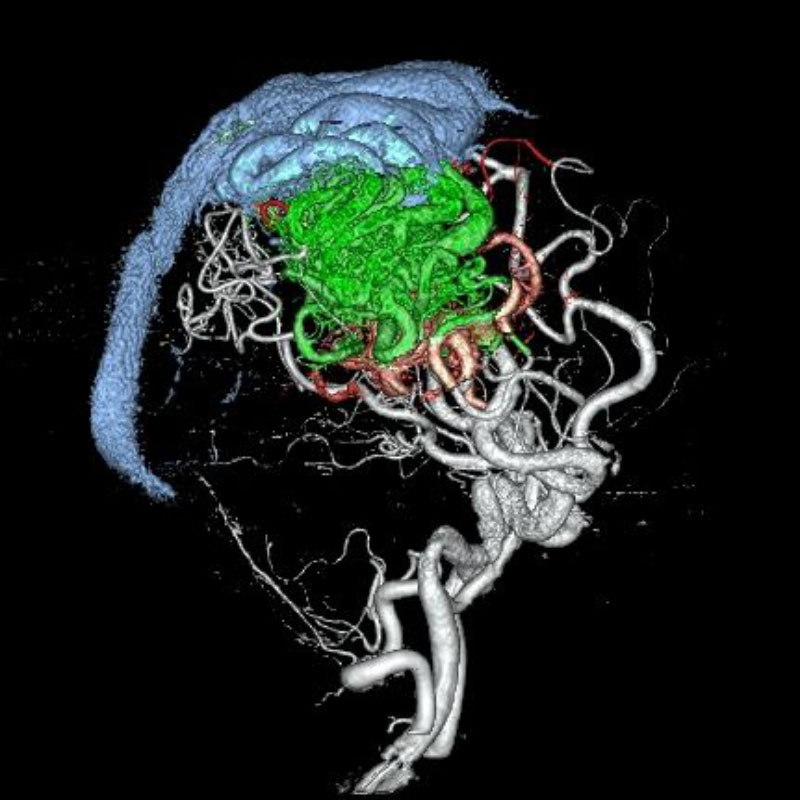

脳動静脈奇形

摘出術

南田/野本/古谷/元永